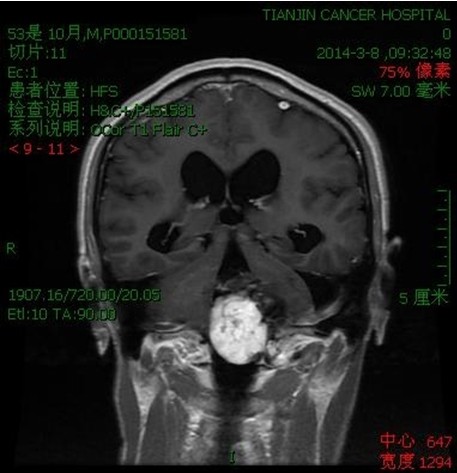

病例二:王**,男性,53岁。因做小脑肿瘤术后9年,头痛头晕,伴颈部疼痛、走路不稳半年入院。入院诊断:延颈交界血管网织细胞瘤。术式:后正中入路延颈交界区血管网织细胞瘤切除术。术后病理:血管网织细胞瘤。术后头痛头晕,颈部疼痛消失,走路平稳。

术前